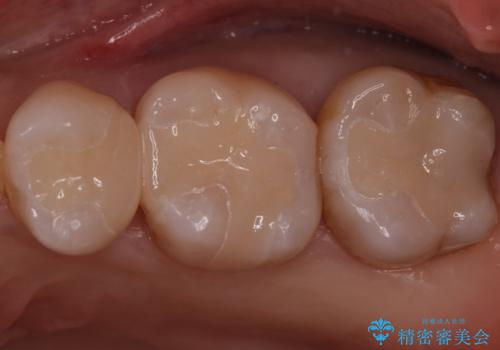

銀歯を白くしたい セラミックインレーでのやり替え

特に大きな虫歯もなかったため、周りの歯を残しつつセラミックインレーでの修復処置をしていきます。

- 左上567 セラミックインレー:77,000円×3本費用は治療当時の料金となります

大きな虫歯さえなければ、銀歯のやり替えは詰め物の周りの歯を保存しつつ修復することができます。